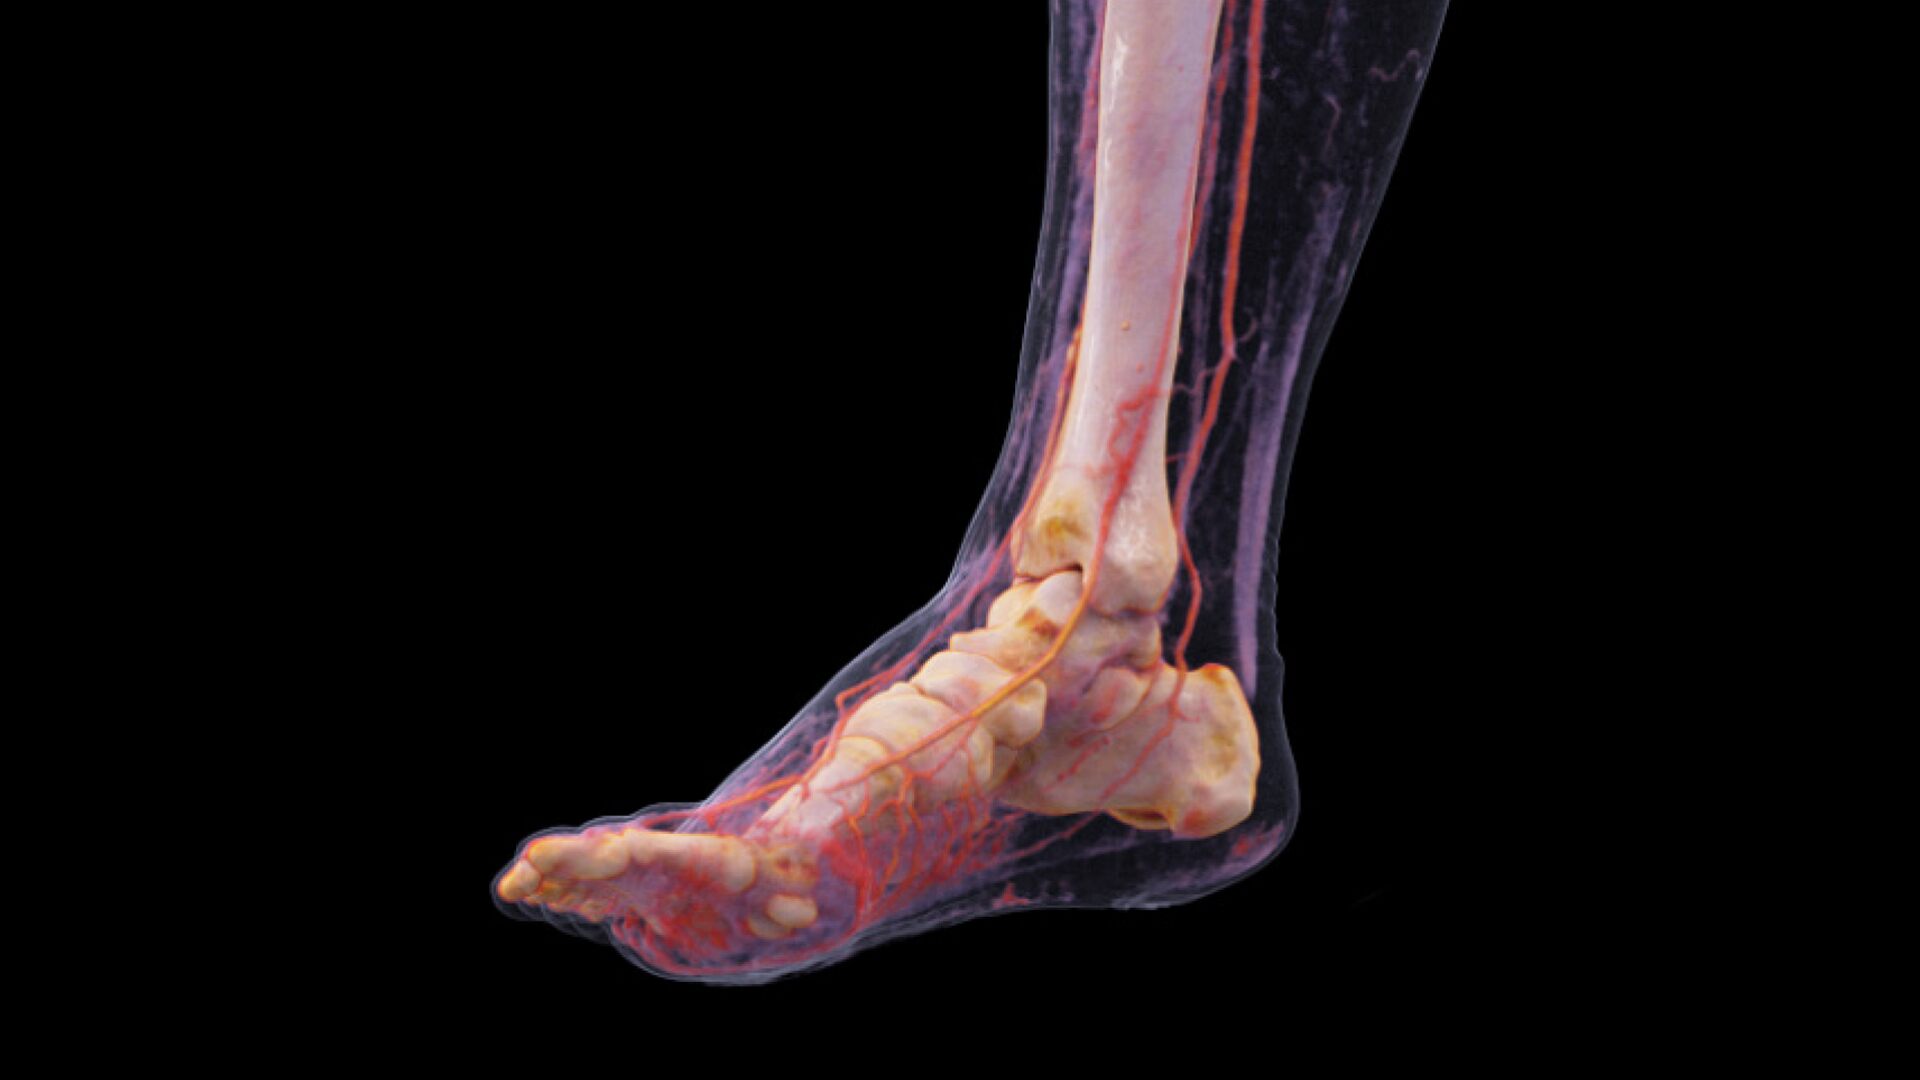

Расширенная до 80 см динамическая КТ ангиография

Проводите функциональные исследования, такие как перфузия тела и динамическая КТ ангиография ультрадлинных диапазонов при низкой лучевой нагрузке.